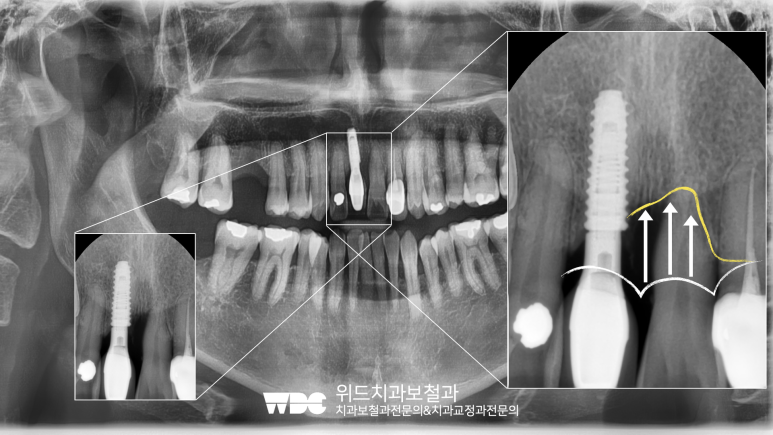

처음 내원하신 상태인데요,

아래사진을 보시면 흰색 화살표로 표시된 것이

문제가 되는 치아입니다.

육안으로 봤을때는 크게 문제가 없어보이는데요,

아래 방사선사진을 보시면 문제가 명확하게 드러납니다.

치아를 지지해주는 치조골이 전반적으로 소실되어서

치아가 많이 흔들리고 통증을 유발한 것입니다.

아래사진의 오른쪽 확대한 부분을 보시면,

흰색라인이 이상적인 치조골의 위치라면

현재 환자분은 노란색라인과 같이

치조골이 심하게 흡수되어 있는 상태였습니다.